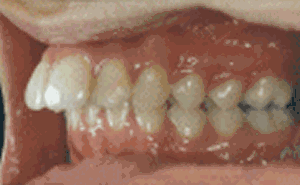

其实“龅牙”是东方人种中较为常见的一类牙颌面畸形,在医学专业上实质是上颌前突畸形或双颌前突畸形,一般不伴有严重的功能障碍,但非常影响美观,患者求治的目的主要是为了改善容貌。寇主任说,现在不用再为自己的龅牙苦恼啦,成人龅牙完全可以通过美容冠进行修复。

龅牙是较为常见的一类牙颌面畸形,龅牙非常影响美观,很多成人朋友希望通过龅牙矫正来改善他们的容貌、牙齿咬合状况,能够拥有灿烂的微笑。但是龅牙美容冠的矫正方法在不同的年龄阶段可以采用不同的方式:

美容冠的矫正龅牙是一种目前流行于欧美日韩的新兴牙齿美容技术,该技术在传统烤瓷牙的基础上强调牙齿的美容效果,针对成人错位牙、畸形牙的临床冠部分施以专业手段,较后用美容冠加以修复。具有美牙不拔牙,无痛苦,时间短,牙齿坚固,多年后牙龈不会出现黑线等优点,从而达到终生有保障的美牙效果。